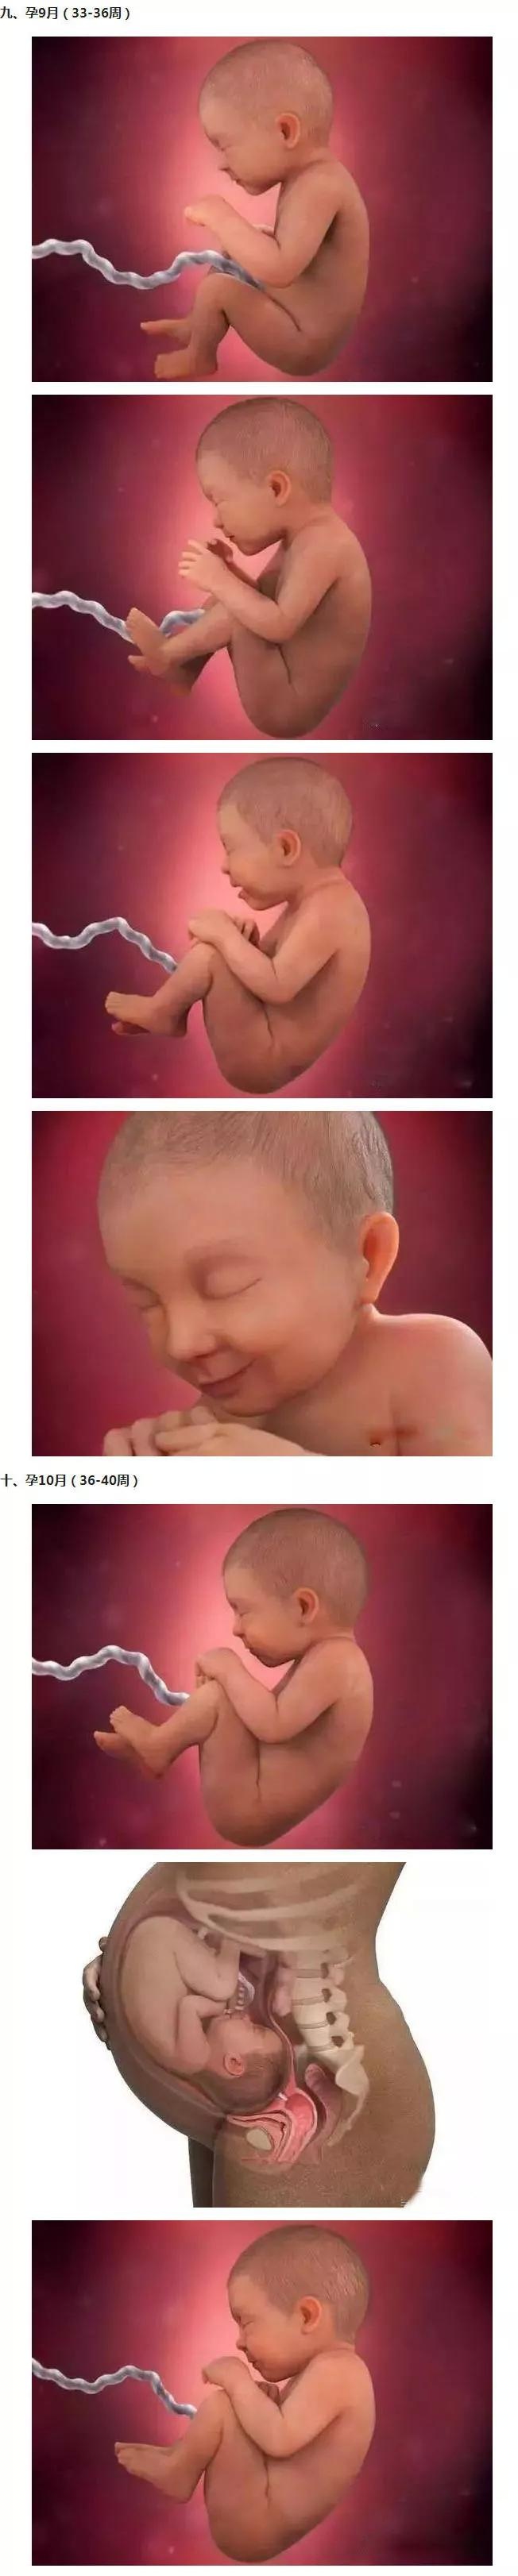

胎儿40周发育全程高清图!原来胎儿是这样成长的!

图片尺寸652x3244

怀孕40周胎宝宝每周长啥样

怀孕40周胎儿每周发育情况是怎样的看完你就涨知识了